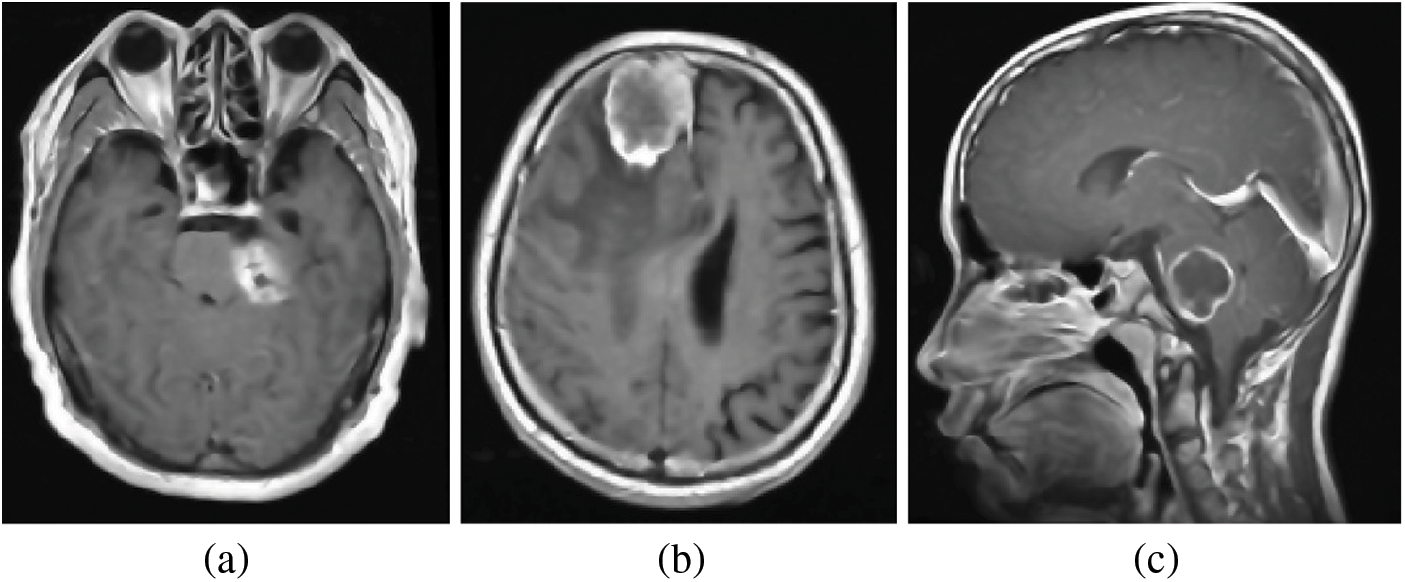

The processing of brain MRI images is a pivotal component of the pre-processing phase in our proposed method. In this phase, the emphasis is on enhancing the quality of brain MRI data and reducing noise levels through image processing. The study involved processing MRI scans from three different planes: axial, sagittal, and coronal, these are obtained from the CE-MRI database, as depicted in the accompanying Fig. 3.

Figure 3: Brain MRI scans from various perspectives: (a) Axial View, (b) Sagittal View, and (c) Coronal Views